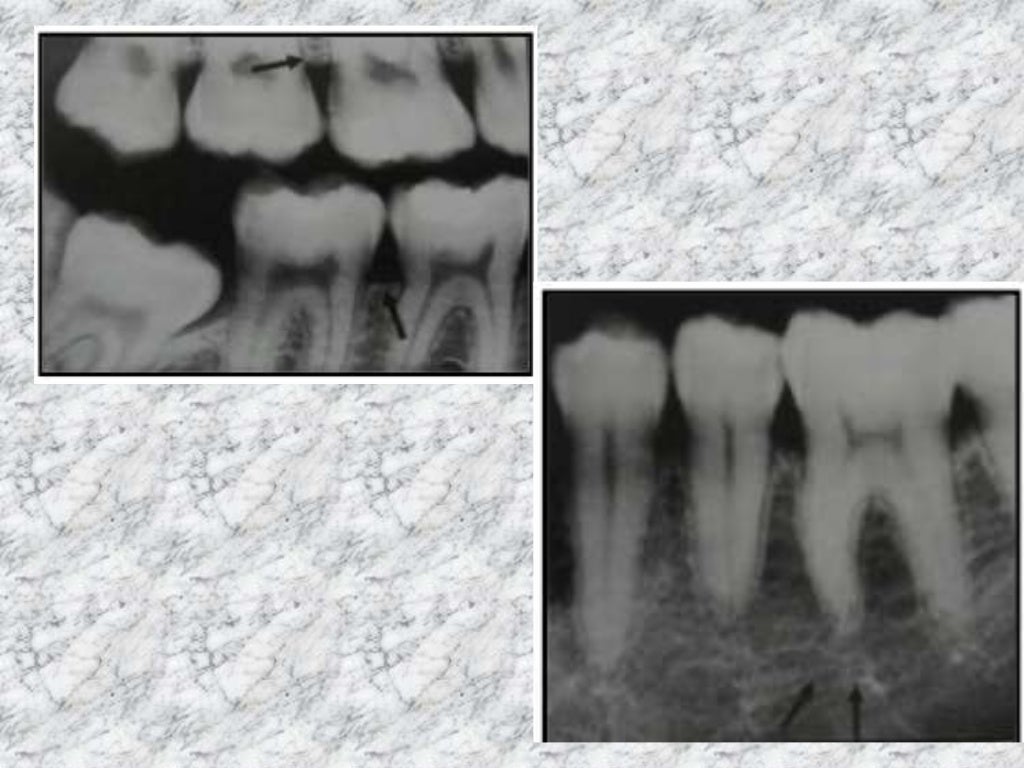

Mixed radiopaque & radiolucent lesions of jaw Most Radiopaque Nonodontogenic radiolucencies tend to be. What is the most radiopaque. What is the most radiolucent material? periapical radiolucencies are most commonly odontogenic. by understanding the significance of radiopaque materials in imaging processes, both healthcare. The radiopacity values of gradia direct loflo, dentin and estelite flow q were close to that of 1 mm al. what determines an. Most Radiopaque.